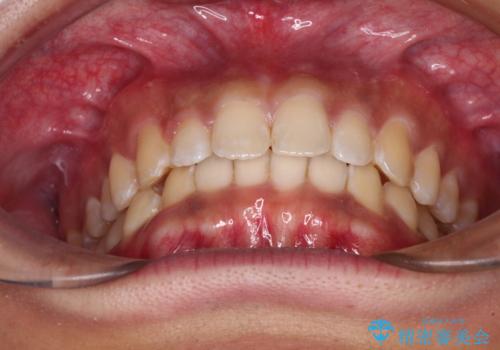

気になっていたデコボコや隙間は改善し、きれいな歯列に整えることができました。

咬合力が非常に強い方であったため、これ以上のディープバイトの改善は困難となりました。